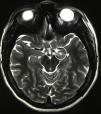

Materials and methodsEight paediatric patients met strict criteria for IND and were enrolled in this study. Electroencephalography (EEG), video electroencephalography (VEEG) and magnetic resonance imaging (MRI) were performed in all patients prior to surgery. Irreducible neuroagressive symptom was approached by lesional therapy based on most described targets for this disorder and assessed by the Overt Aggression Scale (OAS) pre-operatively and 6 months following surgery, using Wilcoxon test for statistical analysis.

Results and conclusionsThe average patient age was 13 years 2 months. 7 of the 8 patients enrolled had intellectual disabilities, 1 patient suffered neurologic sequelae referable to Dandy–Walker syndrome and 7 patients had no preoperative anatomical alterations. Following surgery, patients with IND noted improvement in their OAS. On average, the OAS improved by 39.29% (p=.0156), a figure similar in comparison to studies assessing treatment of IND in adult patients. The most satisfactory results were achieved in patients whose ablative therapy involved the Amygdala in their targets. There were no deaths or permanent neurological deficits attributable to procedure. To the author's knowledge, this is the largest series described in the literature for paediatric patients with IND treated with lesional stereotactic therapy.